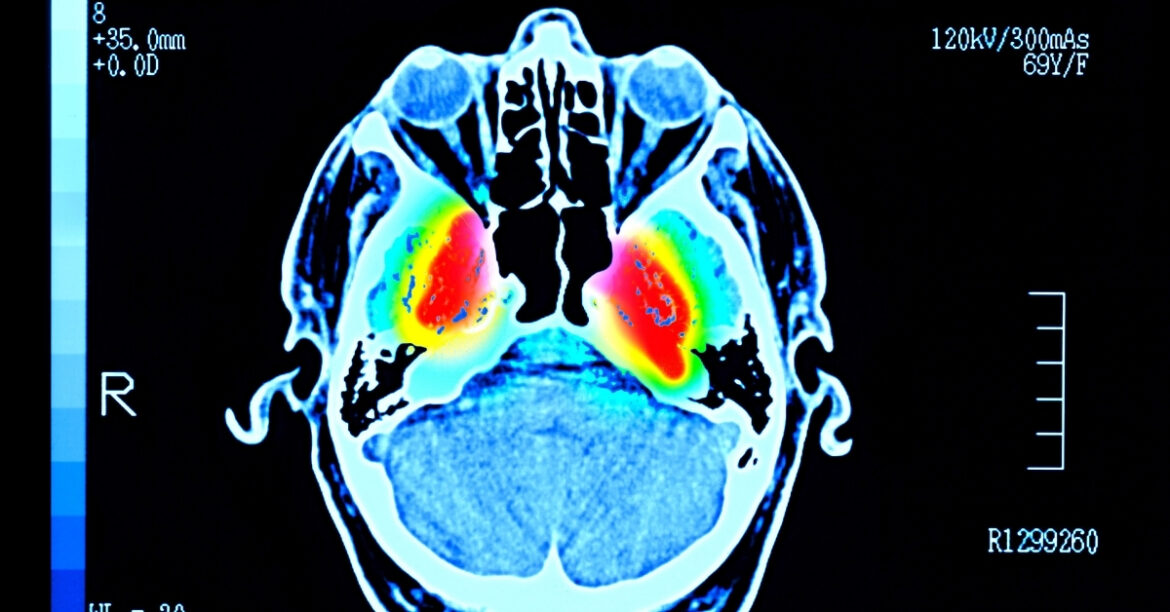

Sumitomo says that this is more than just a theoretical treatment. A clinical trial led by Kyoto University involved seven patients, aged 50 to 69, who got millions of these engineered cells injected into both hemispheres of their brains.

Those test subjects have experienced no significant side effects two years later, and more than half of the participants showed improved motor symptoms.